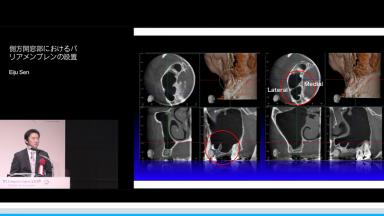

側方開窓部におけるバリアメンブレンの設置

Eiju Sen

本講演では,上顎洞底挙上術の一手法である側方開窓術の術前臨床的判断基準,術式詳細,臨床経過,CBCT所見,術後偶発症,文献的考察から,開窓部へのバリアメンブレン設置を整理する.